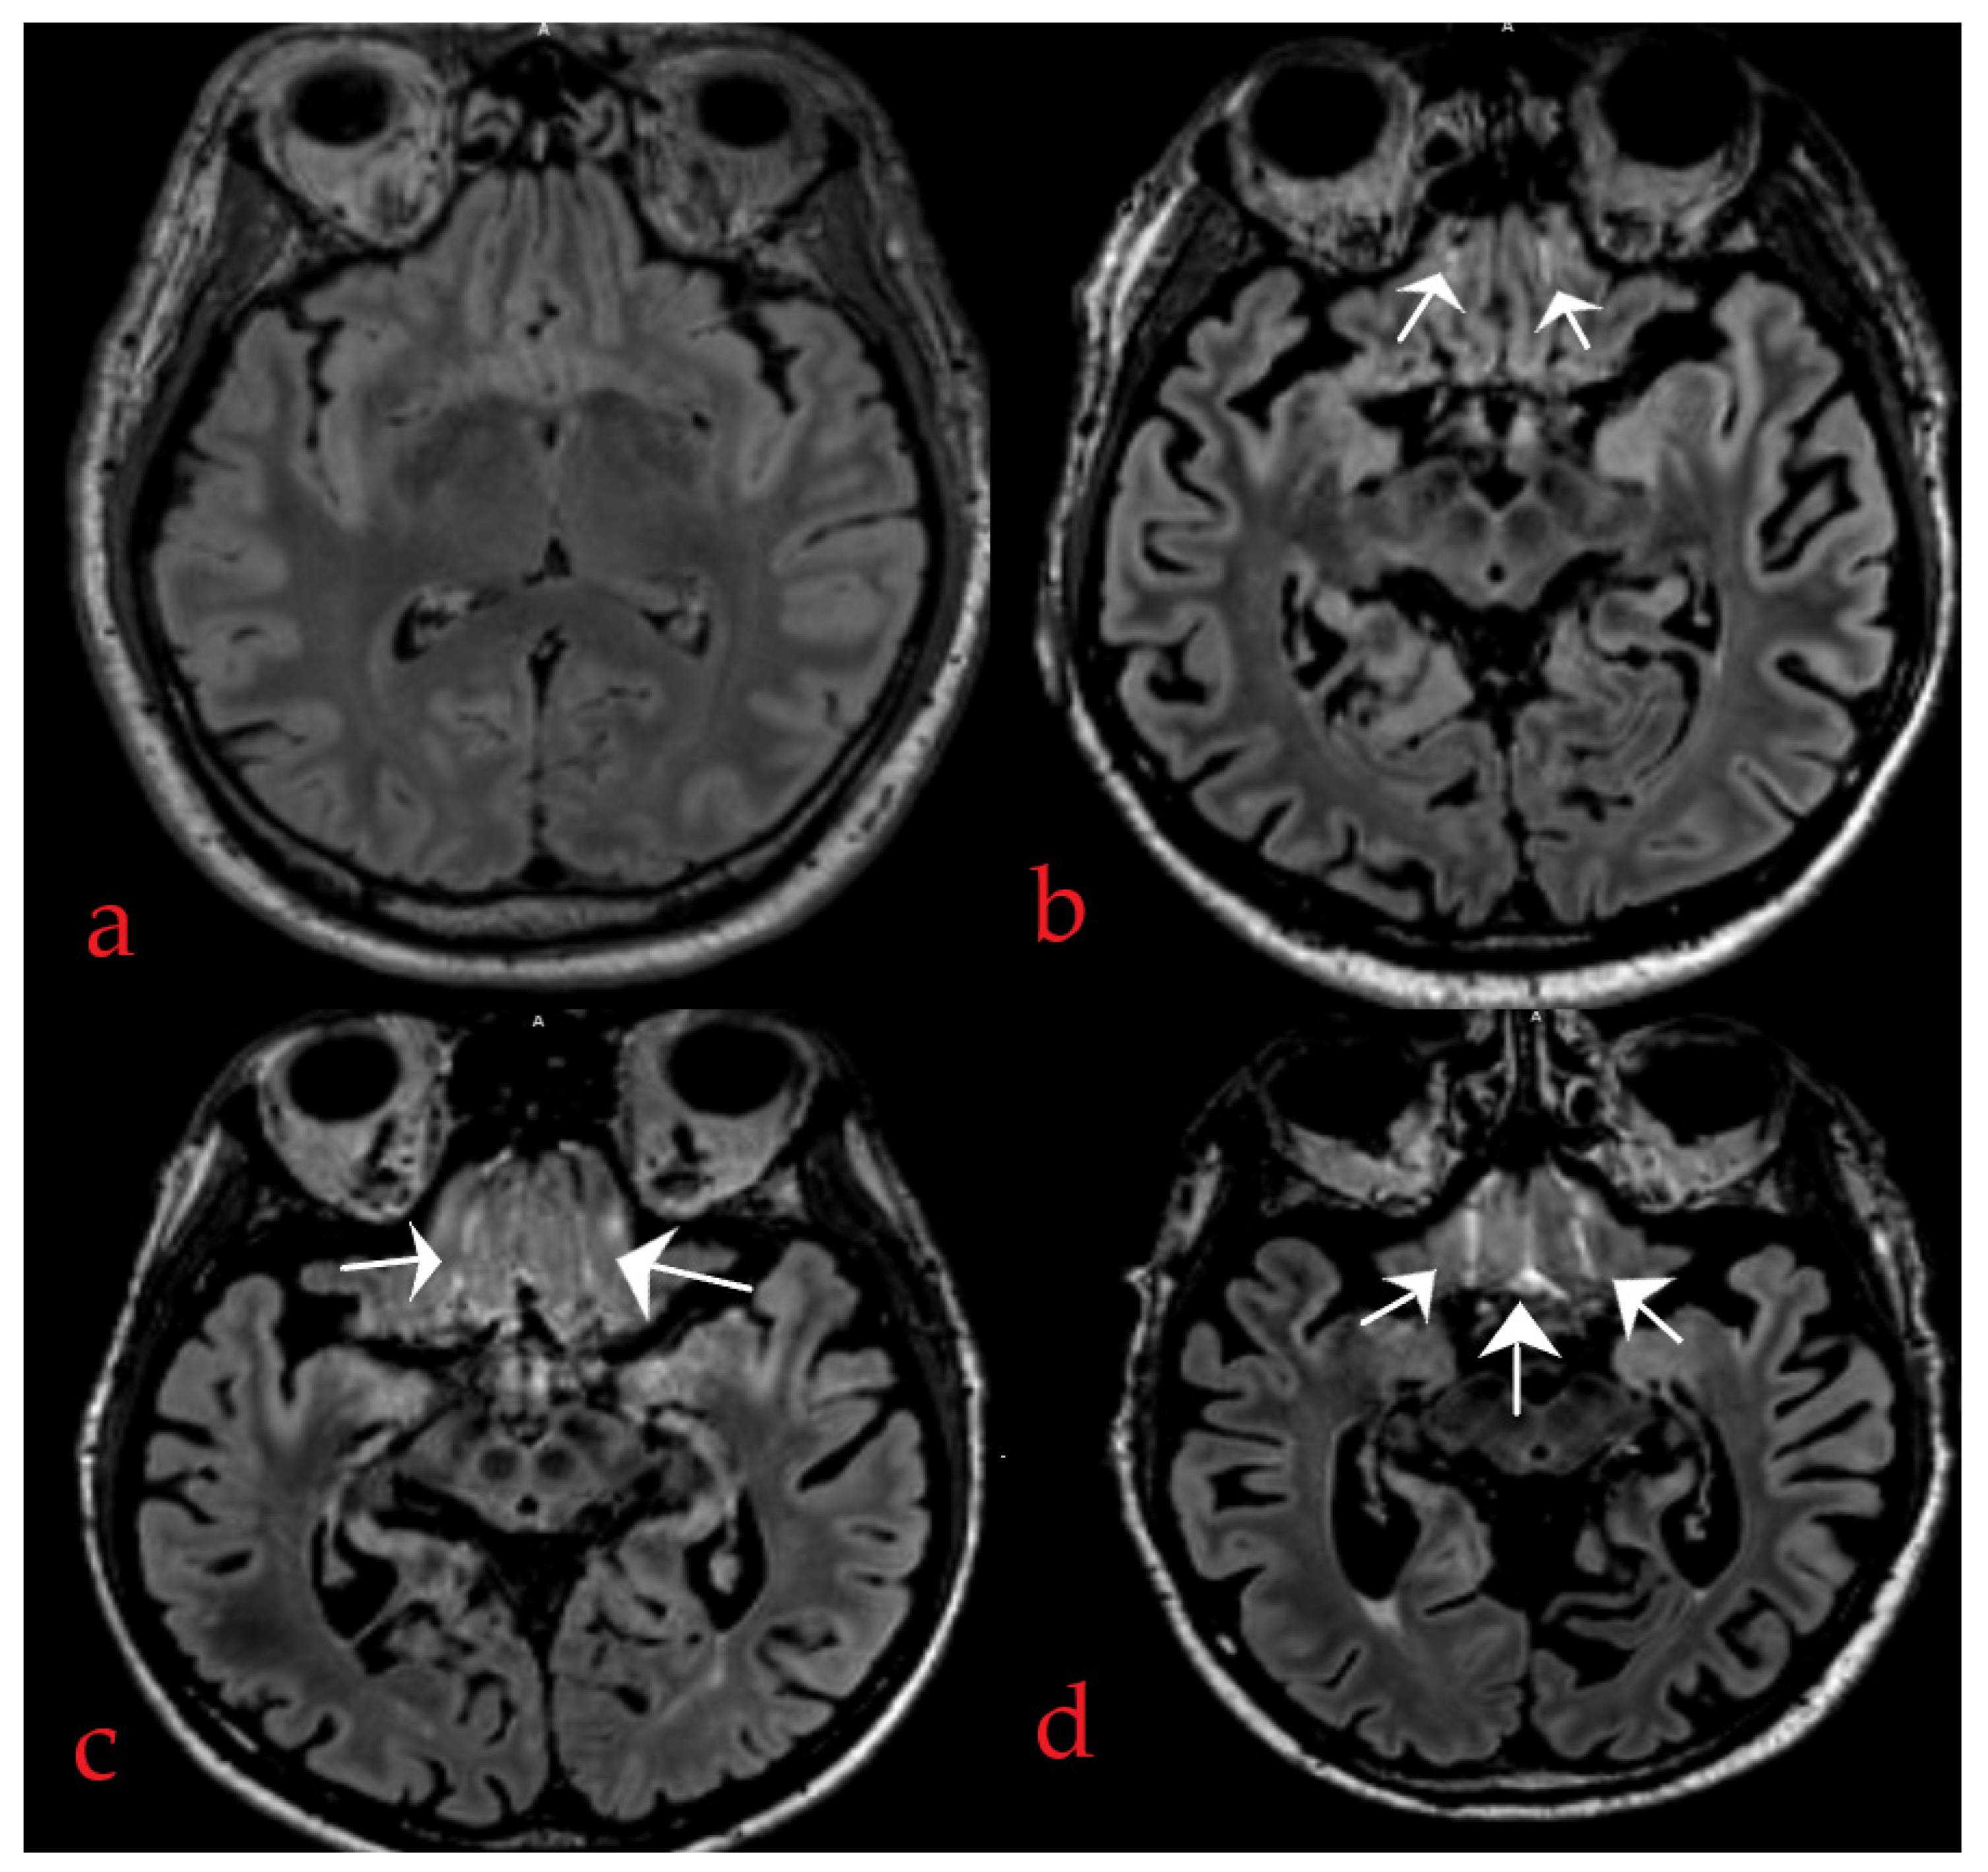

2.4. Method of IFSHs Rating